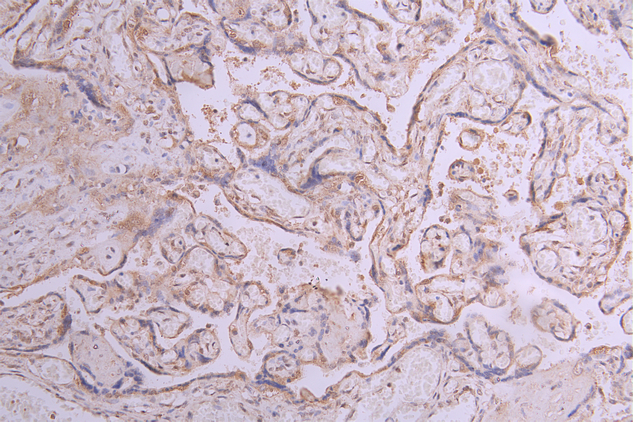

IHC image of CSB-RA011868MA1HU diluted at 1:50 and staining in paraffin-embedded human placenta tissue performed on a Leica BondTM system. After dewaxing and hydration, antigen retrieval was mediated by high pressure in a citrate buffer (pH 6.0). Section was blocked with 10% normal goat serum 30min at RT. Then primary antibody (1% BSA) was incubated at 4°C overnight. The primary is detected by a Goat anti-human polymer IgG labeled by HRP and visualized using 0.05% DAB.